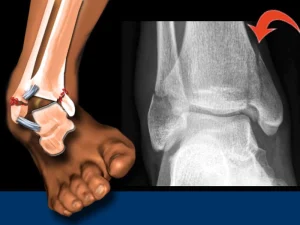

دررفتگی مچ پا زمانی اتفاق میافتد که استخوانهای مچ پا از جای طبیعی خود خارج شده و رباطها آسیب ببینند. این اتفاق بعد از زمین

شکستگی مچ پا زمانی رخ می دهد که یک یا چند استخوان در مفصل مچ پا دچار آسیب و ترک خوردگی شوند. این عارضه معمولا